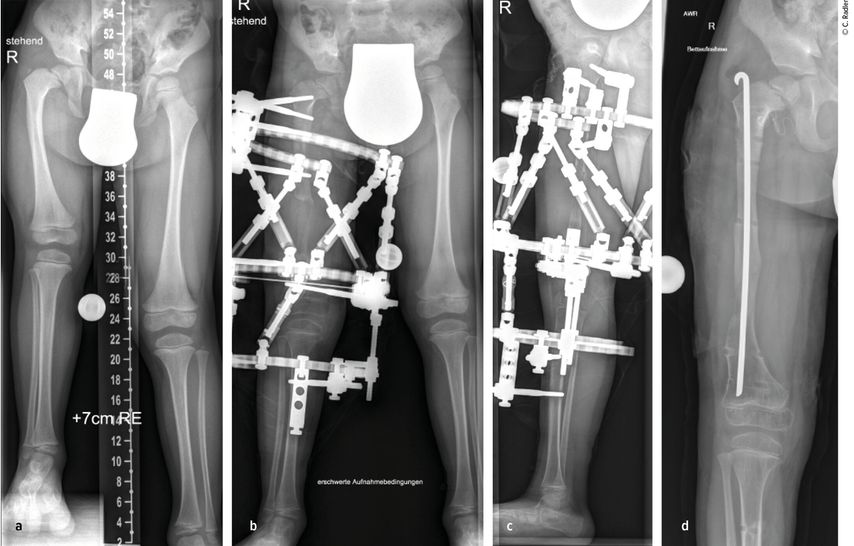

Der kongenitale Femurdefekt ist eine der spannendsten und komplexesten angeborenen Fehlbildungen in der Kinderorthopädie und in der klinischen Präsentation sehr vielgestaltig. Während auf den ersten Blick die Verkürzung des Beins/des Femurs augenscheinlich ist, sind es die assoziierten Veränderungen an Hüfte und Kniegelenk, welche die Therapie herausfordernd machen und vor einer Verlängerung adressiert werden müssen.

Zu den angeborenen Längsdefekten der unteren Extremität zählen neben dem kongenitalen Femurdefekt (CFD) die Fibulahemimelie (FH) und die Tibiaaplasie/-hemimelie. Der Femurdefekt reicht von einer milden Verkürzung des Femurs bis zu seinem fast vollständigen Fehlen, und auch die Fibulahemimelie kann sich von einer milden Verkürzung des Unterschenkels bis zu einer massiven Verkürzung mit schweren Veränderungen am Sprunggelenk präsentieren. Der CFD und die FH kommen fast immer gemeinsam vor, wobei die meisten Fälle eine klare Dominanz der einen oder anderen Pathologie zeigen und die sekundäre Deformität sich oft nur durch minimale Veränderungen an Knochen oder Gelenk präsentiert. Die Tibiaaplasie/-hemimelie ist oft mit Syndromen mit zusätzlichen Fehlbildungen oder Duplikaturen an Hand und Fuß verbunden. Diese Form ist mit einer Inzidenz von 1:1000000 sehr selten.